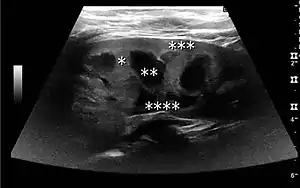

The kidney is divided into parenchyma and renal sinus. The renal sinus is hyperechoic and is composed of calyces, the renal pelvis, fat and the major intrarenal vessels. In the normal kidney, the urinary collecting system in the renal sinus is not visible, but it creates a heteroechoic appearance with the interposed fat and vessels. The parenchyma is more hypoechoic and homogenous and is divided into the outermost cortex and the innermost and slightly less echogenic medullary pyramids. Between the pyramids are the cortical infoldings, called columns of Bertin (Figure 1). In the pediatric patient, it is easier to differentiate the hypoechoic medullar pyramids from the more echogenic peripheral zone of the cortex in the parenchyma rim, as well as the columns of Bertin (Figure 2).[1]

Figure 1. Normal adult kidney. Measurement of kidney length on the US image is illustrated by ‘+’ and a dashed line. *Column of Bertin; ** pyramid; *** cortex; **** sinus.[1]